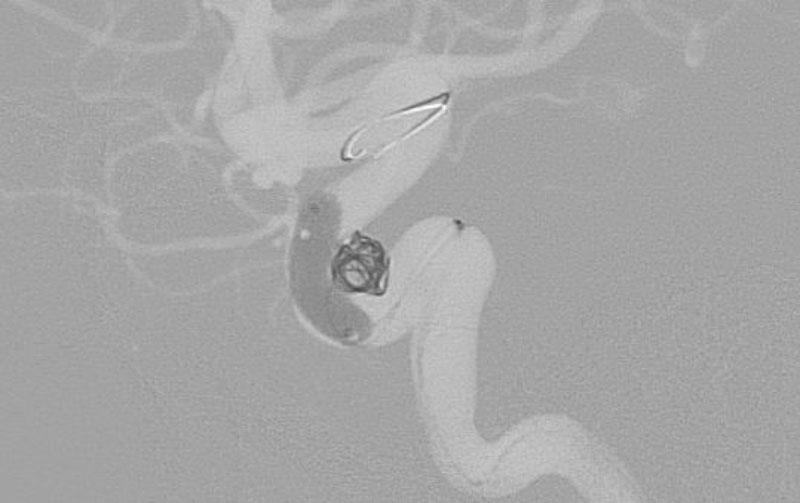

No.1602 手術中